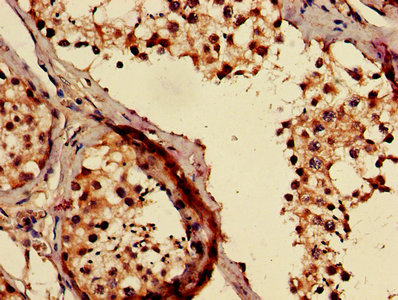

IHC image of CSB-PA891784LA01HU diluted at 1:500 and staining in paraffin-embedded human testis tissue performed on a Leica BondTM system. After dewaxing and hydration, antigen retrieval was mediated by high pressure in a citrate buffer (pH 6.0). Section was blocked with 10% normal goat serum 30min at RT. Then primary antibody (1% BSA) was incubated at 4°C overnight. The primary is detected by a biotinylated secondary antibody and visualized using an HRP conjugated SP system.